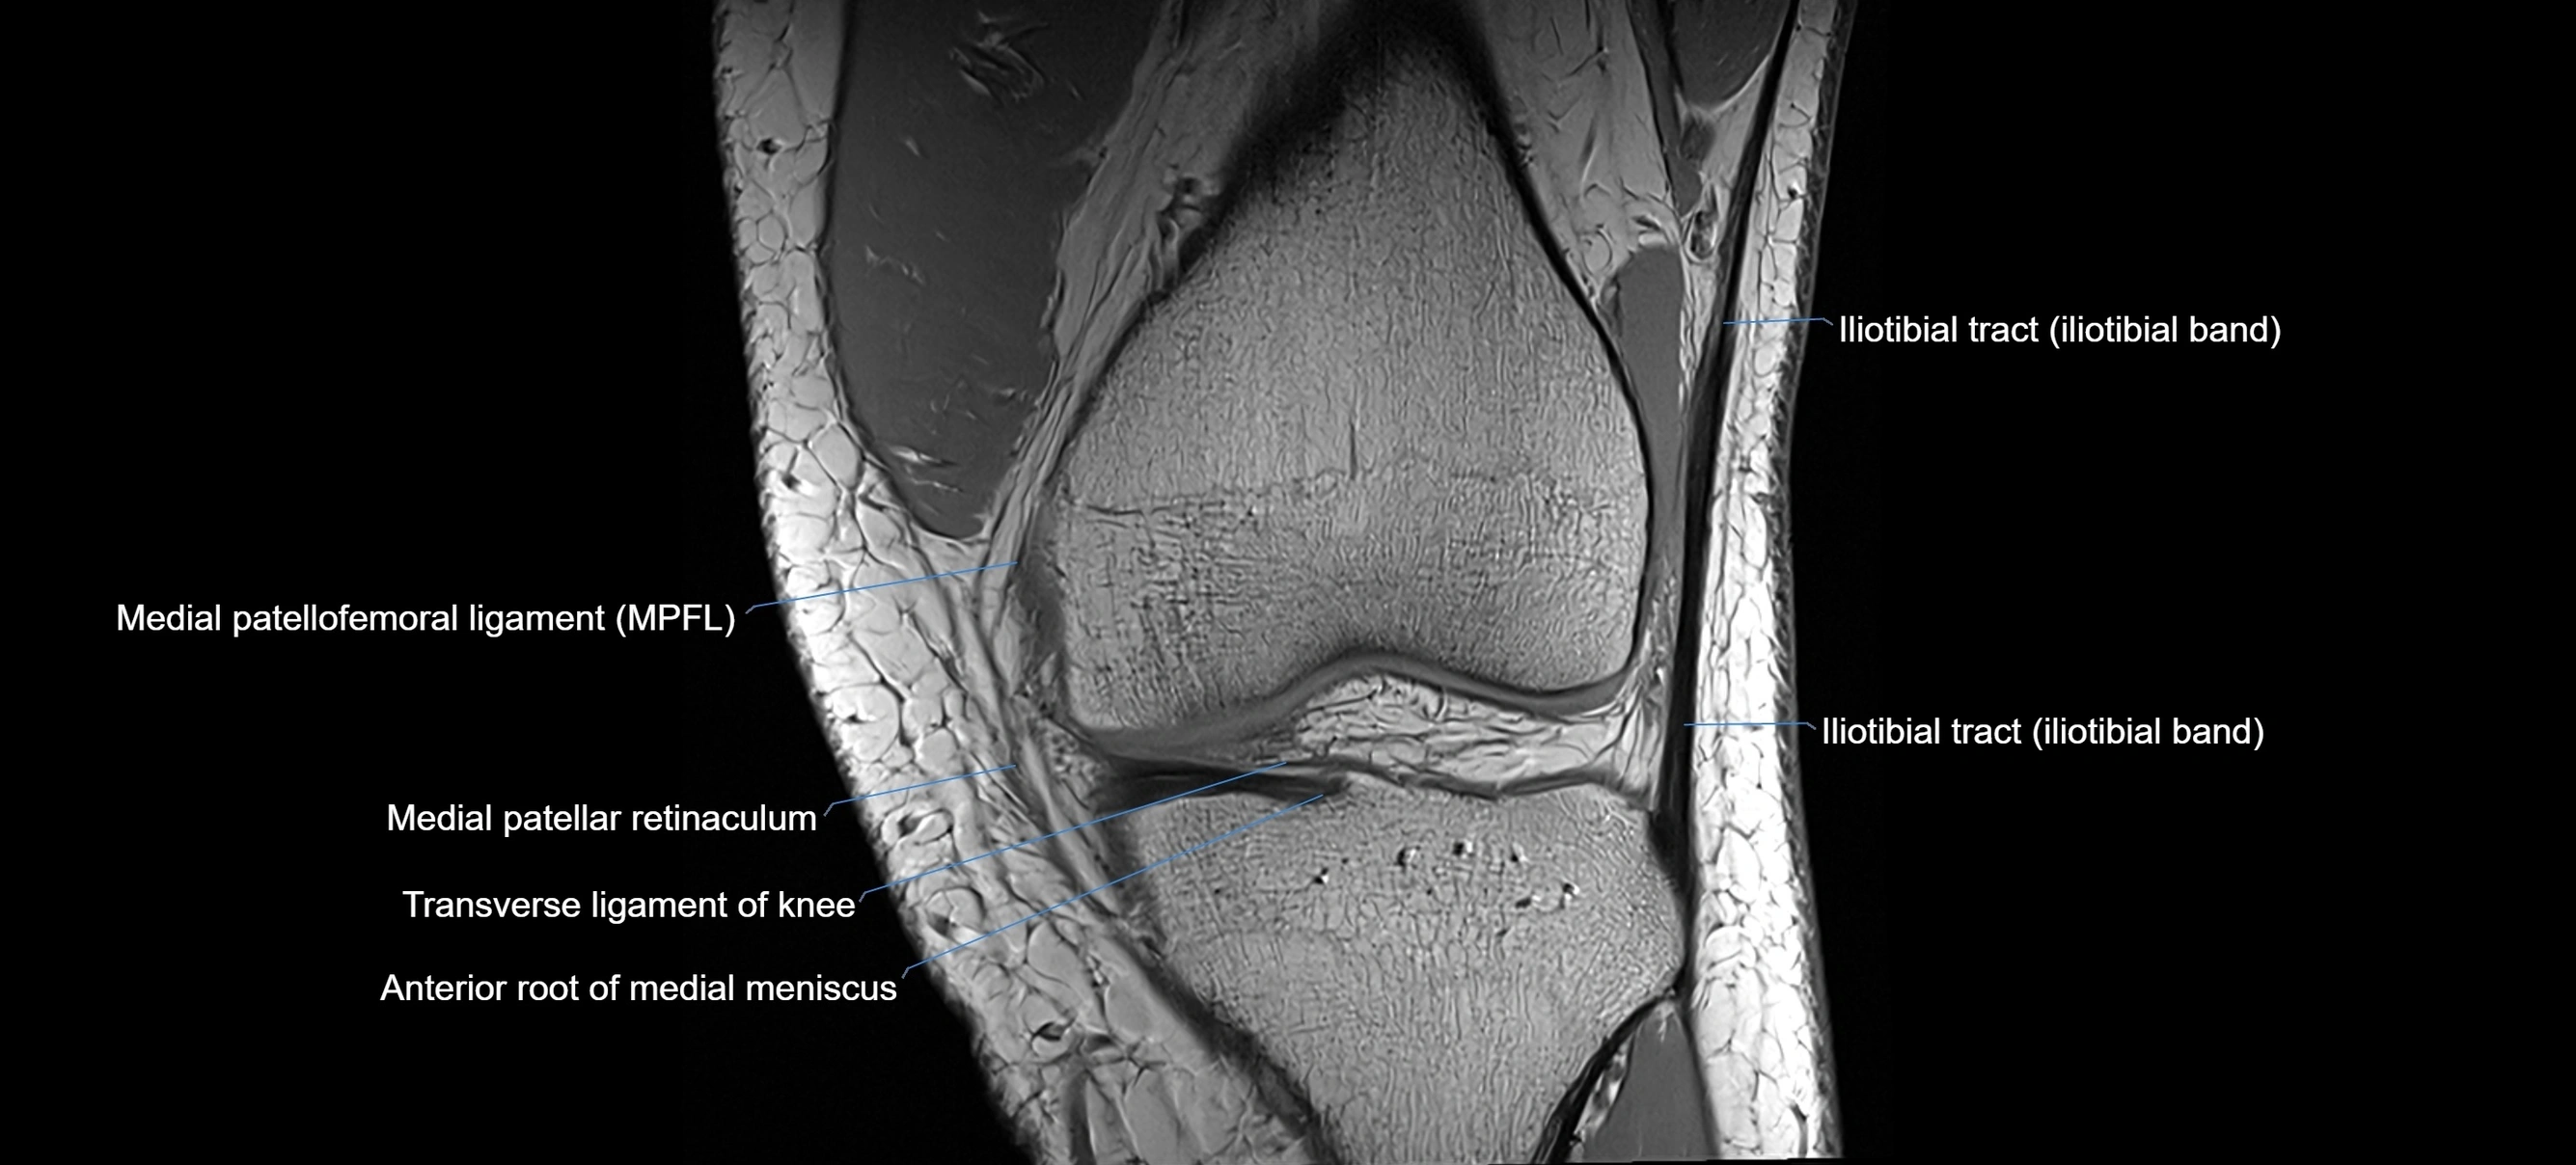

MRI Appearance

T1-weighted images:

• Normal ACL appears as a low-signal band-like structure crossing the intercondylar notch

• Surrounded by intermediate signal synovial fluid and fat planes

T2-weighted images:

• Normal ACL remains low signal

• Partial or complete tears appear as discontinuity, increased signal, or fiber laxity

MRI images

image